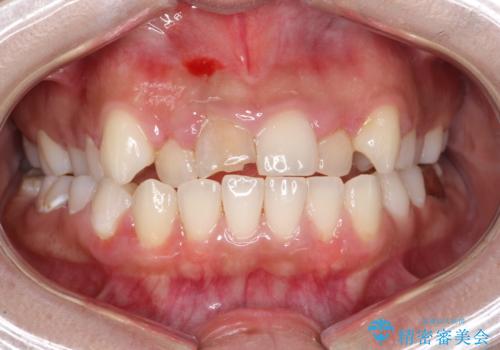

- セラミック矯正希望で来院された患者さんです。

歯周組織の状態が悪く、この状態ではきれいにかぶせものを入れることができないため、仮歯にかえてある程度見た目を改善した上で、歯周基本治療を進めることに。

歯周組織がある程度改善されるまでに3か月ほどかかりました。

いざ型どりしていくというタイミングで、前歯の大きさが違いすぎるのが気になるとのことで歯周外科治療(アピカリ)にて歯肉のラインを整えることに。